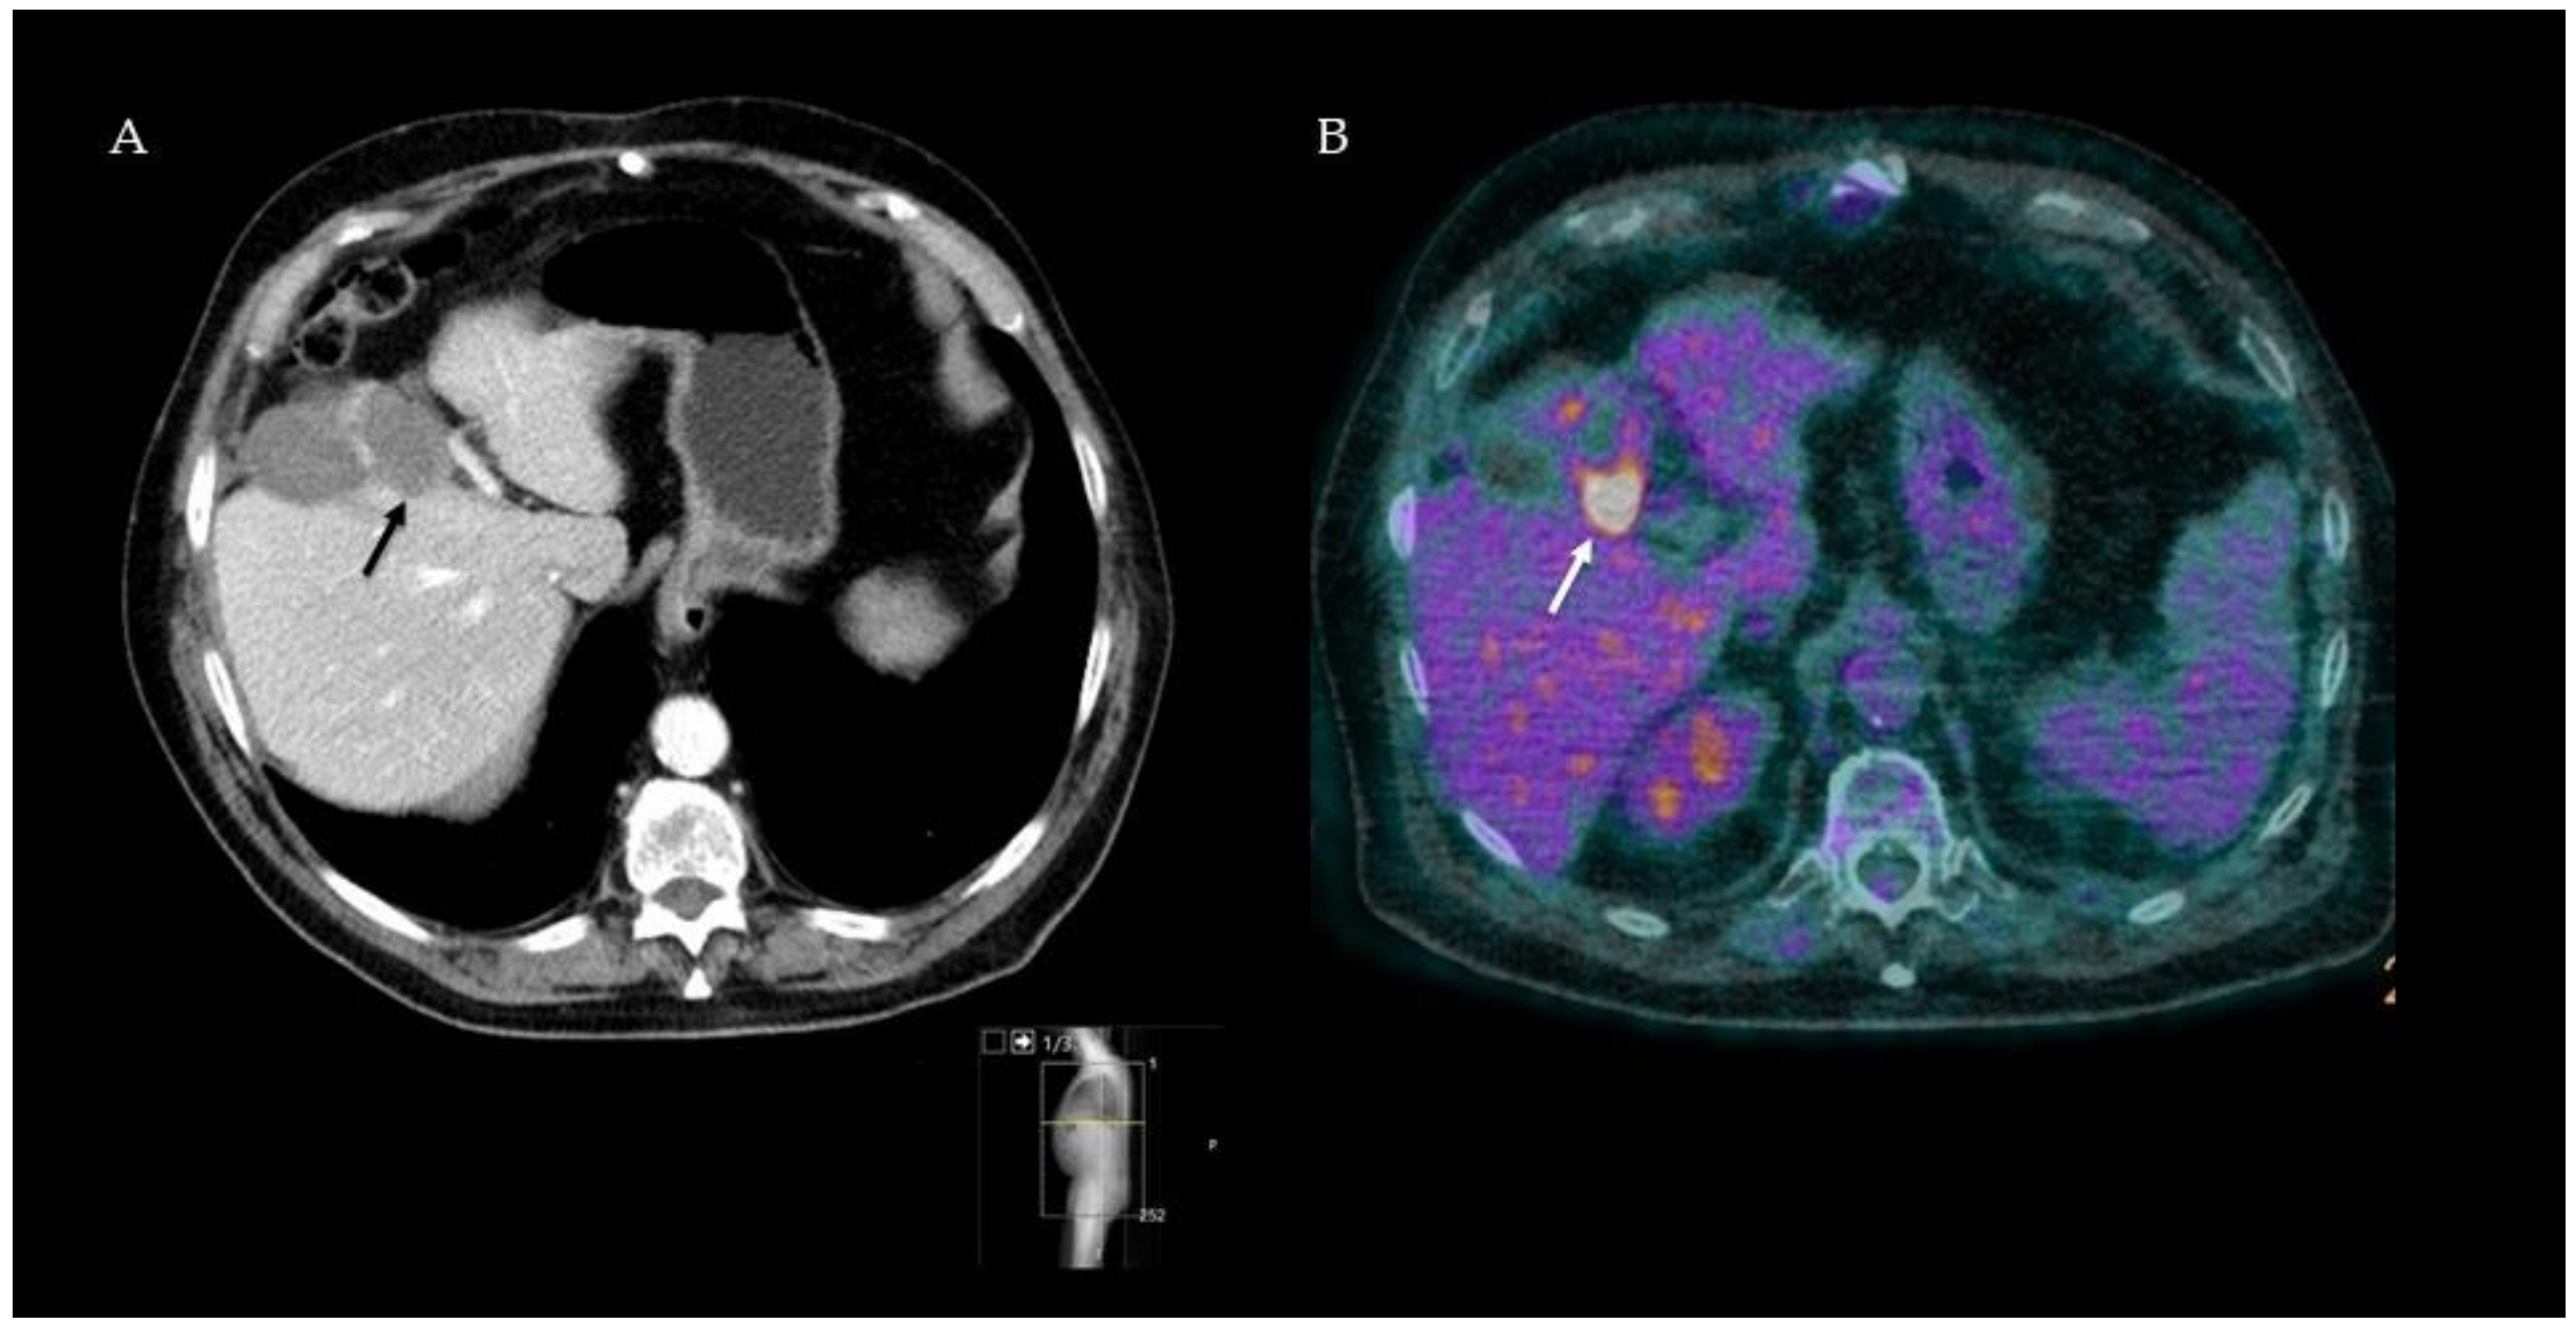

18F-FDG-PET-CT seems to play an important role as a diagnostic imaging modality in the follow-up after thermal ablation of CRLM. In this regard, two strategies can be distinguished: early post-ablation 18F-FDG-PET-CT (i.e., within 24–48 h) and follow-up 18F-FDG-PET-CT 1–3 months after treatment. In general, independent of early (within 48 h) imaging, multiple studies show a clinical superiority of 18F-FDG-PET-CT over ceCT in detecting local tumor progression after thermal ablation. The improved accuracy of follow-up imaging underlines the incremental interest for minimally invasive local ablation therapy. The increased sensitivity resulted in the detection of smaller tumors, which are more amenable to local treatment and which can postpone systemic therapy. An example of the value for detecting residual disease 3 months after ablations is provided in Figure 2, and an overview of included studies and results is summarized in Table 2.

Figure 2.

Follow-up ceCT image three months after RFA, suggesting clear ablation margins (black arrow) and no residual tumor (A). Simultaneous 18F-FDG-PET-CT image of the same patient showing high focal FDG uptake in the tumor periphery (white arrow) strongly suspected of residual disease (B). Three months later, CEA levels had risen, and the focal FDG uptake had spread, confirming tumor residue at the ablation site.